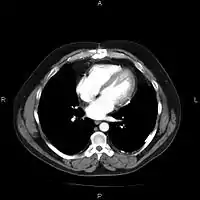

An image as stored on a picture archiving and communication system (PACS)

The same image following contrast adjustment, sharpening and measurement tags added by the system